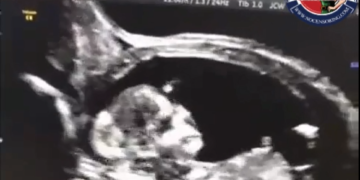

A young pregnant woman injects the second dose of the eugenic vaxx. Three and a half weeks later, she goes to the hospital for doctors to check how the fetus is growing. They tell him that he is dead and that he has been dead inside his body for about three and a half weeks. 331 Views May 15, 2022